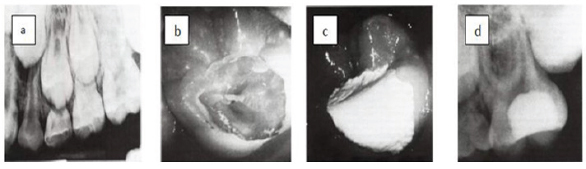

Figure 1: Cesare cesariano.

a) Preoperative radiograph of maxillary first molar showing deep occlusal caries.

b) Caries are removes except a layer immediately over the pulp.

c) CH is applies to caries dentine.

d) Postoperative radiograph after 1 year, the remaining caries are removes and permanent restoration is placed.

The second step, after 6 to 12 months allowing sufficient time for tertiary dentine formation, the carious lesion is reentered and the caries is removed to the formed dentine bridge and permanent restoration is placed [38]. However, what is critical to both steps of excavation is the placement of well sealed restoration [39].